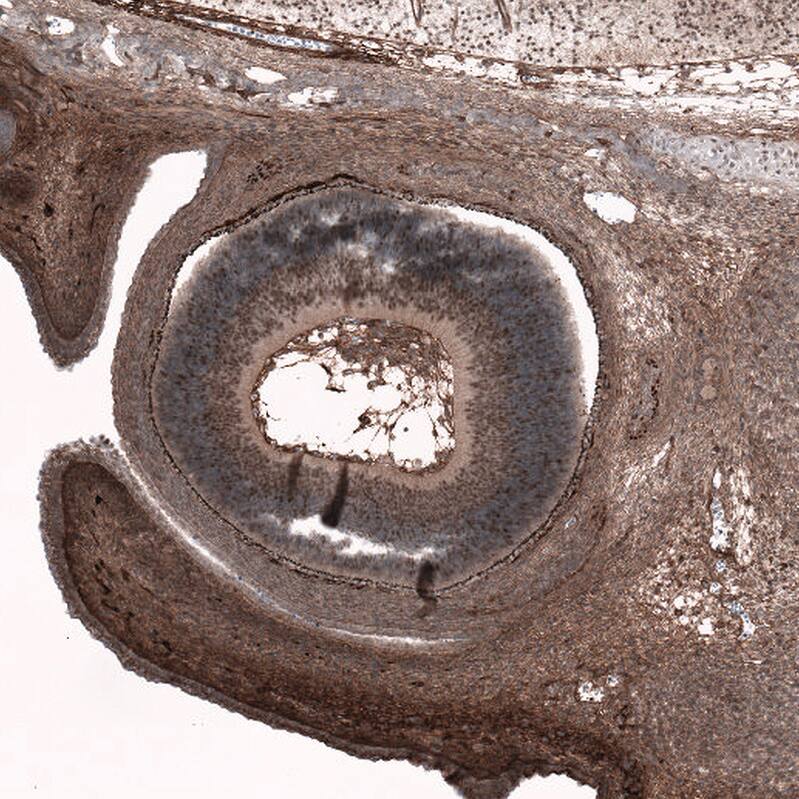

SOX11 Antibody (CL0142) Immunohistochemistry: SOX11 Antibody (CL0142) [NBP3-52058]

Immunohistochemistry: SOX11 Antibody (CL0142) [NBP3-52058]

Staining of human chronic lymphocytic leukemia shows no nuclear positivity in tumor cells as expected.